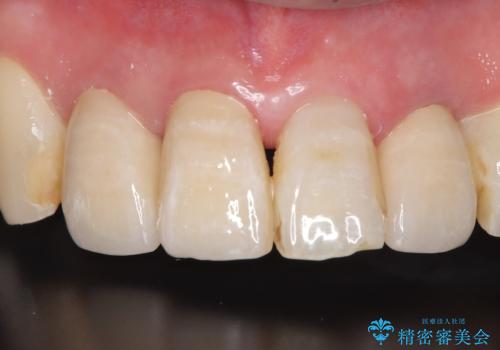

【オールセラミッククラウン】被せ物の色が気になる!

- 「被せ物の色が気になる」を主訴に来院された患者さんです。

保険で治療した被せ物が劣化し色も変色をおこしていました。かつ被せ物と歯の境目(適合)も合っていない状態でした。

古い被せ物を除去しオールセラミッククラウンで治療を行いました。

被せ物の適合が悪く劣化もおこし色が変色している状態でした。そのため他の歯とも色が合っていませんでした。古い被せ物を除去し形を整えた後にオールセラミッククラウンで治療を行いました。